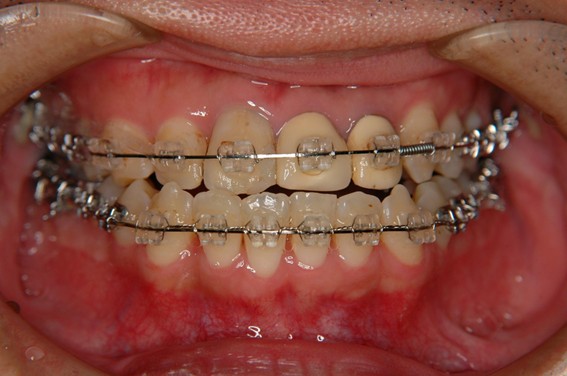

| 主訴 | 前歯が逆に噛んでいるところがある。歯のがたつき。 |

| 治療内容 | 表側ワイヤー矯正、4本抜歯を行いました。 |

| 治療費 | 880,000円+ダイレクトボンディング33,000円(税込) |

| 治療期間 | 30ヶ月 |

| 治療回数 | 30回 |

| 想定されたリスク | 歯根吸収、歯髄壊死、歯髄充血、歯肉退縮のリスクがありました。 |